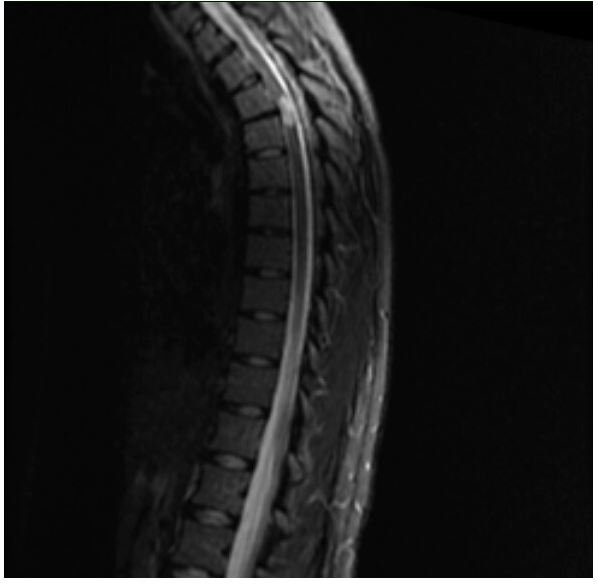

Her initial lab work was unremarkable with the exception of mild hypoglycemia of 63mg/dL, CRP was mildly elevated at 0.60mg/dL with a normal ESR. An MRI of the cervical, thoracic, and lumbar spine revealed a short segment enhancing cord abnormality which was located at the T3-T4 level involving most of the spinal cord. There was minimal disc bulging at the levels of L3-L4, L4-L5, L5-S1 without significant spinal canal stenosis or neural foraminal narrowing. No evidence of spinal cord infarction was observed (Figure 1-3). She was tested for COVID-19 given neurologic manifestations of COVID-19 which was positive. She was admitted to the hospital for workup and management of her symptoms under the Department of Internal Medicine with Neurology consultation.

Figure 2: T1 sequence from thoracic MRI performed 10 days following initial MRI in Figure 1 redemonstrating myelitis at the level of T3-T4.